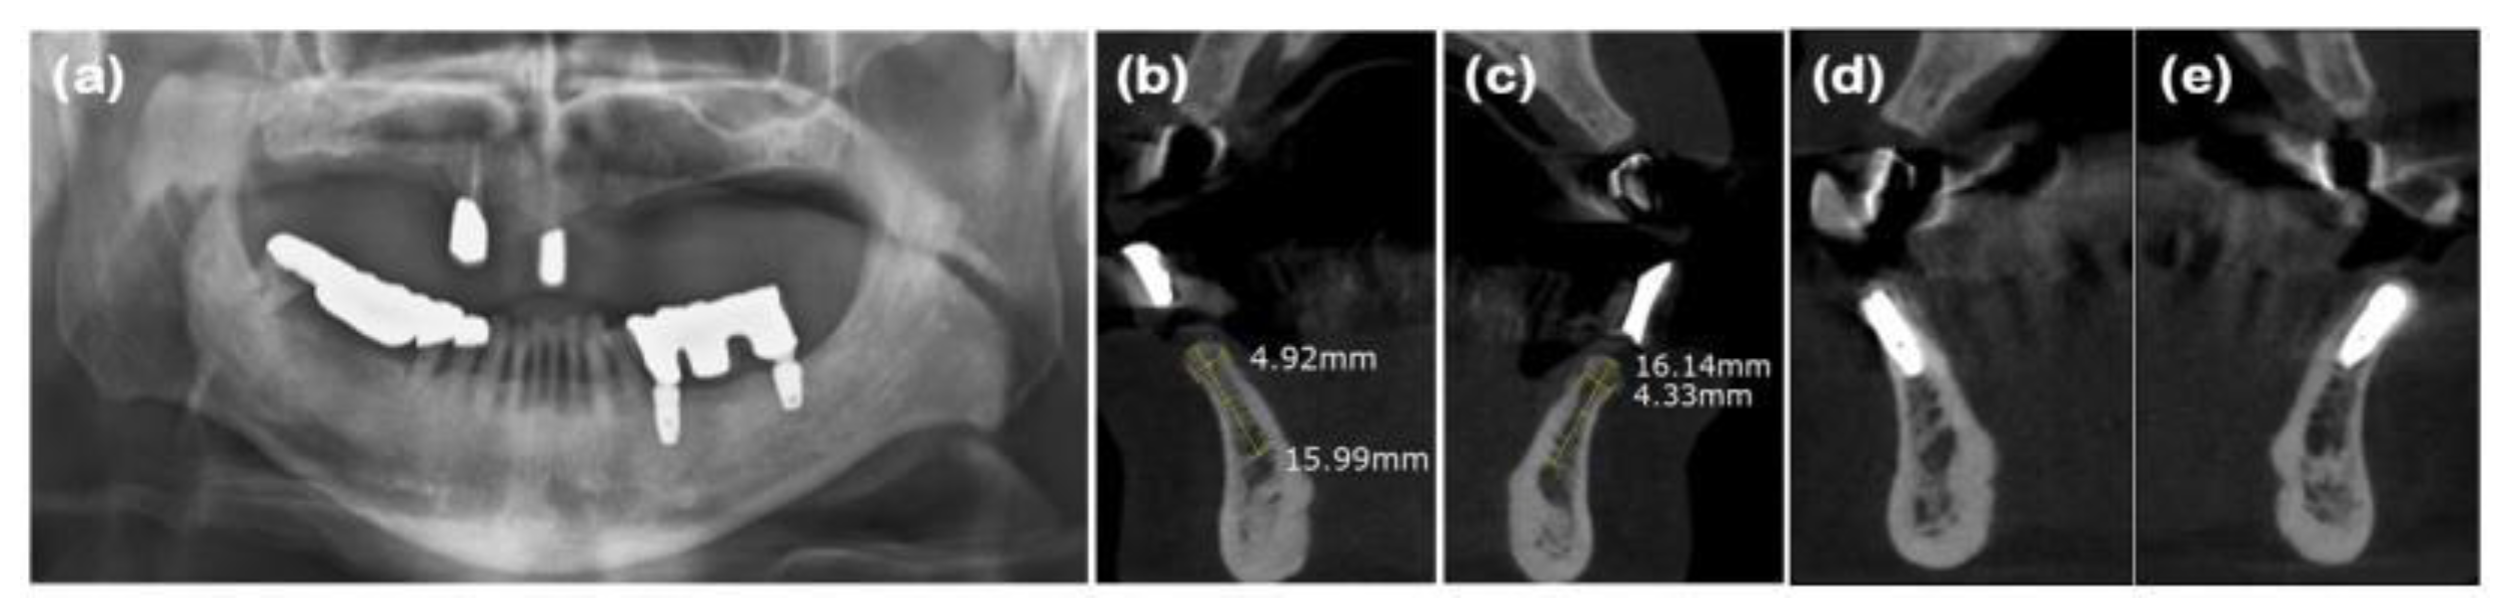

Figure 6. Radiographs of case 3. (a) Pre-operative panoramic view taken during the initial visit. (b and c) CBCT images displaying the augmented site after healing. Alveolar ridge width was measured at approximately 4.92 and 4.33mm on the mandibular right and left lateral incisor areas, respectively, which is sufficient for the placement of a standard diameter implant. (d and e) Implants were placed in the mandibular right and left lateral incisor areas, respectively.

After performing full-mouth scaling, four mandibular anterior teeth were extracted gently. To preserve the interdental papilla after extraction, an incision was made on the lingual side, and the interdental papilla without cutting was included in the full-thickness flap, which was elevated buccally. Buccal bone plate loss was observed (Figure 5a and Figure 6a). Synthetic bone graft material mixed with collagen (Osteon 3 collagen®, Genoss Co., Ltd.) was applied to the extraction site (Figure 5b), and a resorbable collagen membrane (Collagen membrane P®, Genoss Co., Ltd.) was placed over the bone graft. To promote soft tissue regeneration through secondary healing, a xenogenic collagen matrix (Collagen graft®, Genoss Co., Ltd.) was placed over the resorbable collagen membrane and tension-free sutures were applied (Figure 5c). During the healing process, the shape and form of the alveolar bone and interdental papilla, as well as their harmony with the adjacent teeth, were maintained (Figures 5d, 6b, and 6c). Three months after the ARP, the first implant surgery was performed in the #32 and #42 regions (Implantium Φ3.8×10 mm, Dentium) (Figures 5e, 6d, and 6e). A horizontal incision was made slightly on the lingual side, and a full-thickness flap was elevated, revealing 4 mm of augmented bone width. The implant was placed in the ideal position. Every two to three months after the first implant surgery, the preserved shape of the interdental papilla was continuously observed. The second implant surgery was performed 3 months after the first implant surgery, and the prosthesis was placed 4.5 months after the first implant surgery (Figures 5f, 5g, and 5h). Ultimately, the interdental papilla harmonized with the adjacent teeth, and 4 mm of buccal keratinized mucosa was stably observed.

In this study, ARP was performed with flapped surgery in patients who required horizontal and vertical bone augmentation due to the absence of residual bone. A collagen matrix was used to compensate for ridge contraction and to increase the keratinized mucosa around the implants. In case 1, the buccal bone plate at site #23 had been resorbed, resulting in a narrow alveolar ridge width in the bucco-palatal direction, which was insufficient for implant placement. To augment the buccal bone, xenogenic bone graft material, two-types of resorbable collagen membranes, and a xenogenic collagen matrix were applied, sequentially. At the time of implant placement, a ridge width of approximately 5.93mm was observed bucco-palatally, and continuous, intact soft tissue regeneration, including preservation of the interdental papilla, was achieved. In case 2, the bone wall at extraction site #16 had resorbed, necessitating both bone and soft tissue augmentation for predictable implant placement. Periodontal flap surgery was also performed on the adjacent teeth, resulting in a wider incision. A xenogenic collagen matrix was applied to promote adequate soft tissue regeneration. At the time of implant placement, ridge widths of approximately 8.66 and 8.90mm were observed bucco-palatally at sites #16 and #17, respectively, along with a continuous soft tissue contour. In case 3, following the extraction of teeth #31, #32, #41, and #42, the buccal bone plate had been resorbed. After broad ridge augmentation, a xenogenic collagen matrix was applied to aid in soft tissue regeneration and preservation of the interdental papilla. At the time of implant placement, ridge widths of approximately 4.92 and 4.33mm were observed bucco-palatally at sites #32 and #42, respectively, along with continuous soft tissue contour. Upon completion of the implant prosthetics, a natural appearance of the interdental papilla was observed continuously. In case 4, horizontal and vertical alveolar bone defects were observed in explanted sites #46i and #47i, along with a shallow buccal vestibule and insufficient keratinized mucosa. A xenogenic collagen matrix was applied to the buccal and crestal side to ensure sufficient alveolar bone augmentation and keratinized mucosa for implant placement, and the modified Edlan–Mejchar technique was used to deepen the buccal vestibule. At the time of implant placement, ridge widths of approximately 7.90 and 5.58mm were observed bucco-palatally at sites #45 and #47, respectively, while maintaining the natural soft tissue appearance and deepened vestibule. In respect of the anterior teeth in case 1 and case 3, the PES/WES values ​​were measured as 7~8 points, confirming that although the periodontal defects were severe, good esthetic results could be obtained. In the CBCT cross-sectional view and clinical examination of all cases, the alveolar bone width was appropriate for implant placement of narrow diameter or more in the anterior region and regular diameter or more in the posterior region. In addition, the width of the buccal keratinized mucosa was confirmed to be consistently well-maintained at 2 mm or more in all cases. Although there are many opposing views, it is important to secure the presence of keratinized mucosa with more than a 2mm width around the implant for the health and maintenance of the implant [19].